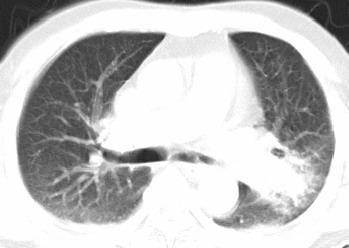

以下是引用xianxianzhongyi在2008-4-20 14:44:00的发言:[br]本人愚见:次病例短短两月的时间,呈现如此大面积实变,病变增长过于迅速,此其一。其二,病变在动脉早期既有明显强化。其三,左上叶后段及下叶背段多叶受累。其四,肺门及纵隔内未见明显肿大的淋巴结。估计层面较厚段支气管显示不清。 诊断:炎性实变可能性大。

以下是引用光影相伴在2008-4-20 14:39:00的发言:[br]支持:1)左侧中央型肺癌伴左肺上叶阻塞性肺炎。、[br] 2)双侧少量胸腔积液。